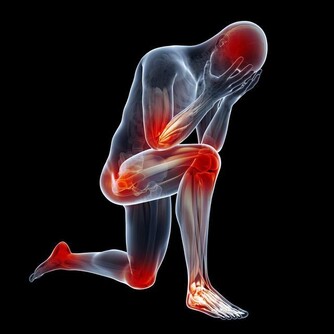

5. 心腦血管病

由於打呼嚕憋氣時人體缺氧,會引起冠狀動脈內皮損傷,脂質在血管內膜沈積,紅細胞增多,血液黏度隨之增加,最終引發各類心腦血管疾病,如:血栓、中風、心絞痛、心肌梗死等,且患者在睡眠中突發心肌梗死和腦梗塞的幾率是正常人群的3倍!

另外,在治療心血管疾病時,不要忽視打呼嚕憋氣對心血管病的危害。